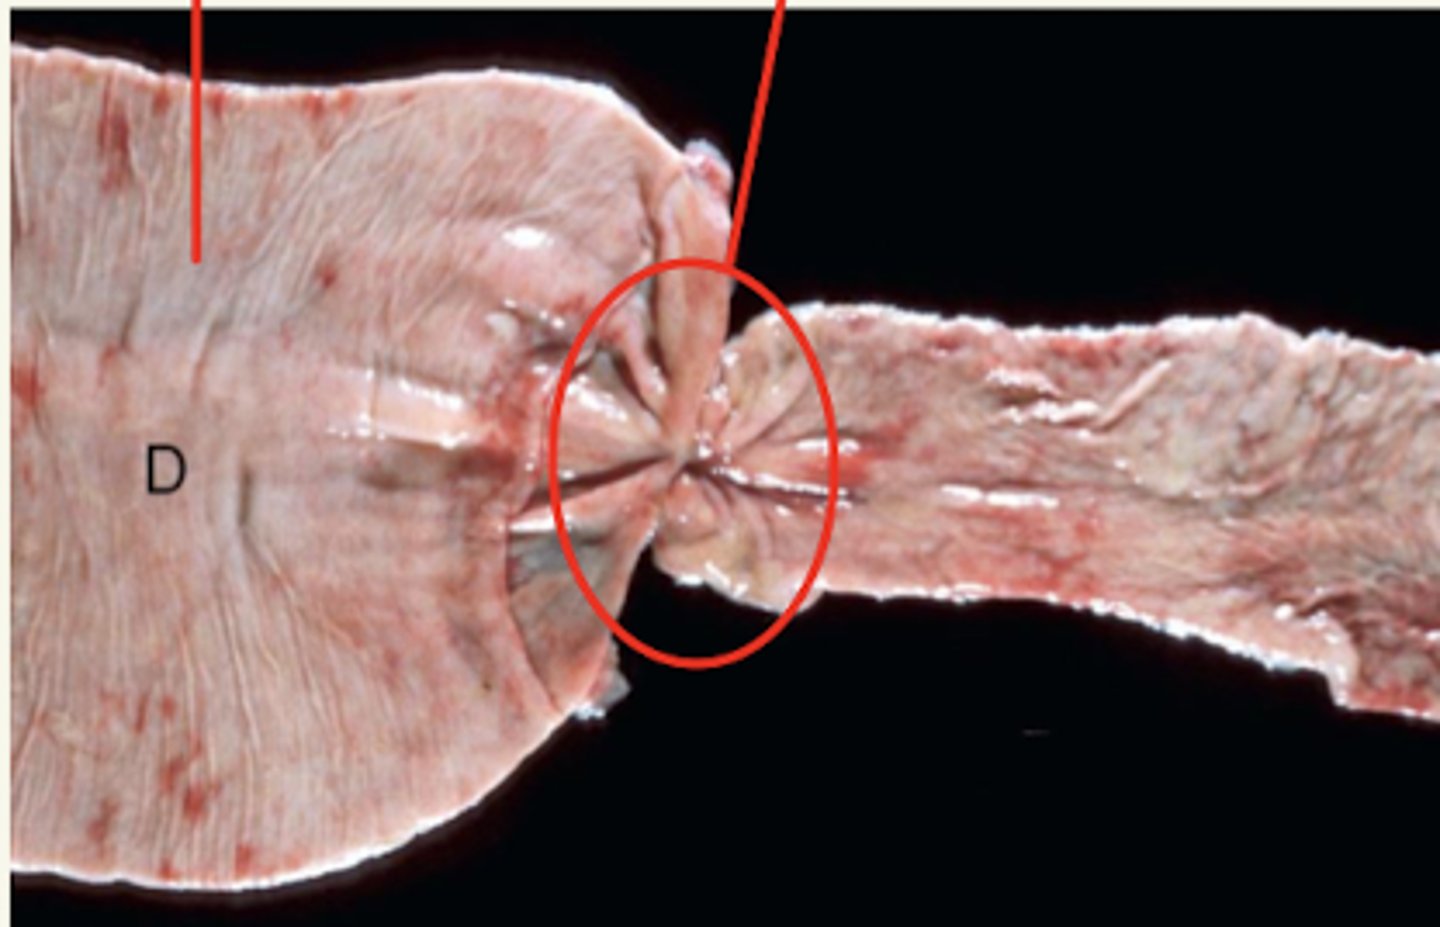

gastritis ulcerativa

¿diagnóstica morfológica?

gastritis ulcerativa por Gasterophilus

¿diagnóstica morfológica y etiológica?